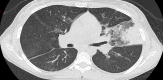

Case report: A young woman with history of asthma presented with complaints of nausea, vomiting, abdominal pain, wheezing, and dry cough. Physical examination revealed diffuse expiratory wheezing and mild diffuse abdominal pain without rebound or guarding. Laboratory results showed leukocytosis with eosinophilia. Stool studies showed Strongyloides stercoralis. Imaging revealed ground-glass opacities in the right upper and lower lobe along with an infiltrate in the lingular lobe on the left side. Bronchoscopy showed Strongyloides stercoralis. The patient was diagnosed with hyperinfection syndrome due to Strongyloides stercoralis most probably exacerbated by prednisone given for her asthma. Steroids were then discontinued and the patient was started on ivermectin. The patient improved with treatment. Repeat stool examination was negative for Strongyloides stercoralis.